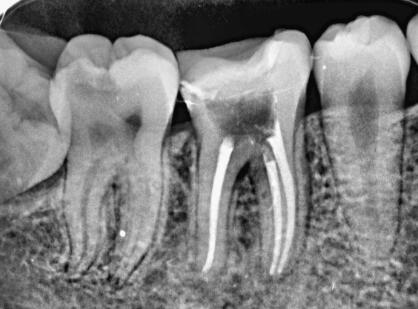

根管治疗是治疗牙神经发炎的手术操作,可以更好的治疗牙龈的发炎现象以及牙髓炎的症状,由于整个操作流程都是在根管之内,所以被称作根管治疗。根管治疗的操作流程并没有很繁琐和复杂,主要分为4个步骤,首先是对牙髓以及牙神经进行一定的清理和疏通,然后再进行消毒,达到去除细菌、炎症的目的。经过消毒之后再填充根管治疗材料能够让整个人的口腔状态更加的健康,后面一部是封闭根管,因此整个治疗流程并没有很繁琐和复杂,但是要找一个更加专业的医院和医生进行针对性的操作,不能够盲目的开展治疗。